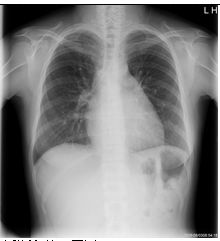

5. 29歲女性,主訴近年來有進展性雙腳水腫,全身倦怠,同時伴有運動性呼吸困難及腹部腫脹。病人在十多年前有紅斑性狼瘡,也因此四處求醫,誤信草藥,終致腎病末期之尿毒,施行血液透析治療。於今年4月24日赴中國接受腎臟移植,不意術後有諸多併發症,如尿路感染等,回國一直在門診治療。近多月來,上述症狀逐漸加劇,乃住院診療。理學檢查:血壓96/55 mmHg;心跳75/min規則;呼吸 18/min,尚屬平穩,病人呈現慢病狀,臉色蒼白,頸靜脈怒張,有Kussmaul's sign,胸部未有濕濁聲,心臟之point of maximal impulse (PMI)不清,S1及S2尚屬正常,未有心雜音,腹部未有肝脾可觸知,雙下肢有水腫。實驗室有WBC,5520;RBC,3,010,000;Hb,10.1 g/dl,BUN,40 mg/dl;Creatinine,1.79mg/dl,餘皆正常。其他胸部X光、心電圖及心臟電腦斷層 如圖示。請問本病人最可能的診斷是: (A) 左心臟衰竭 (B) 右心臟衰竭 (C) 冠心症 (D) 心肌病變 (E) 窄縮性心包膜炎 (constrictive pericarditis)